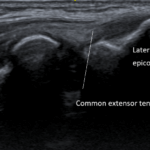

05 외상과염(테니스엘보) lateral epicondylitis